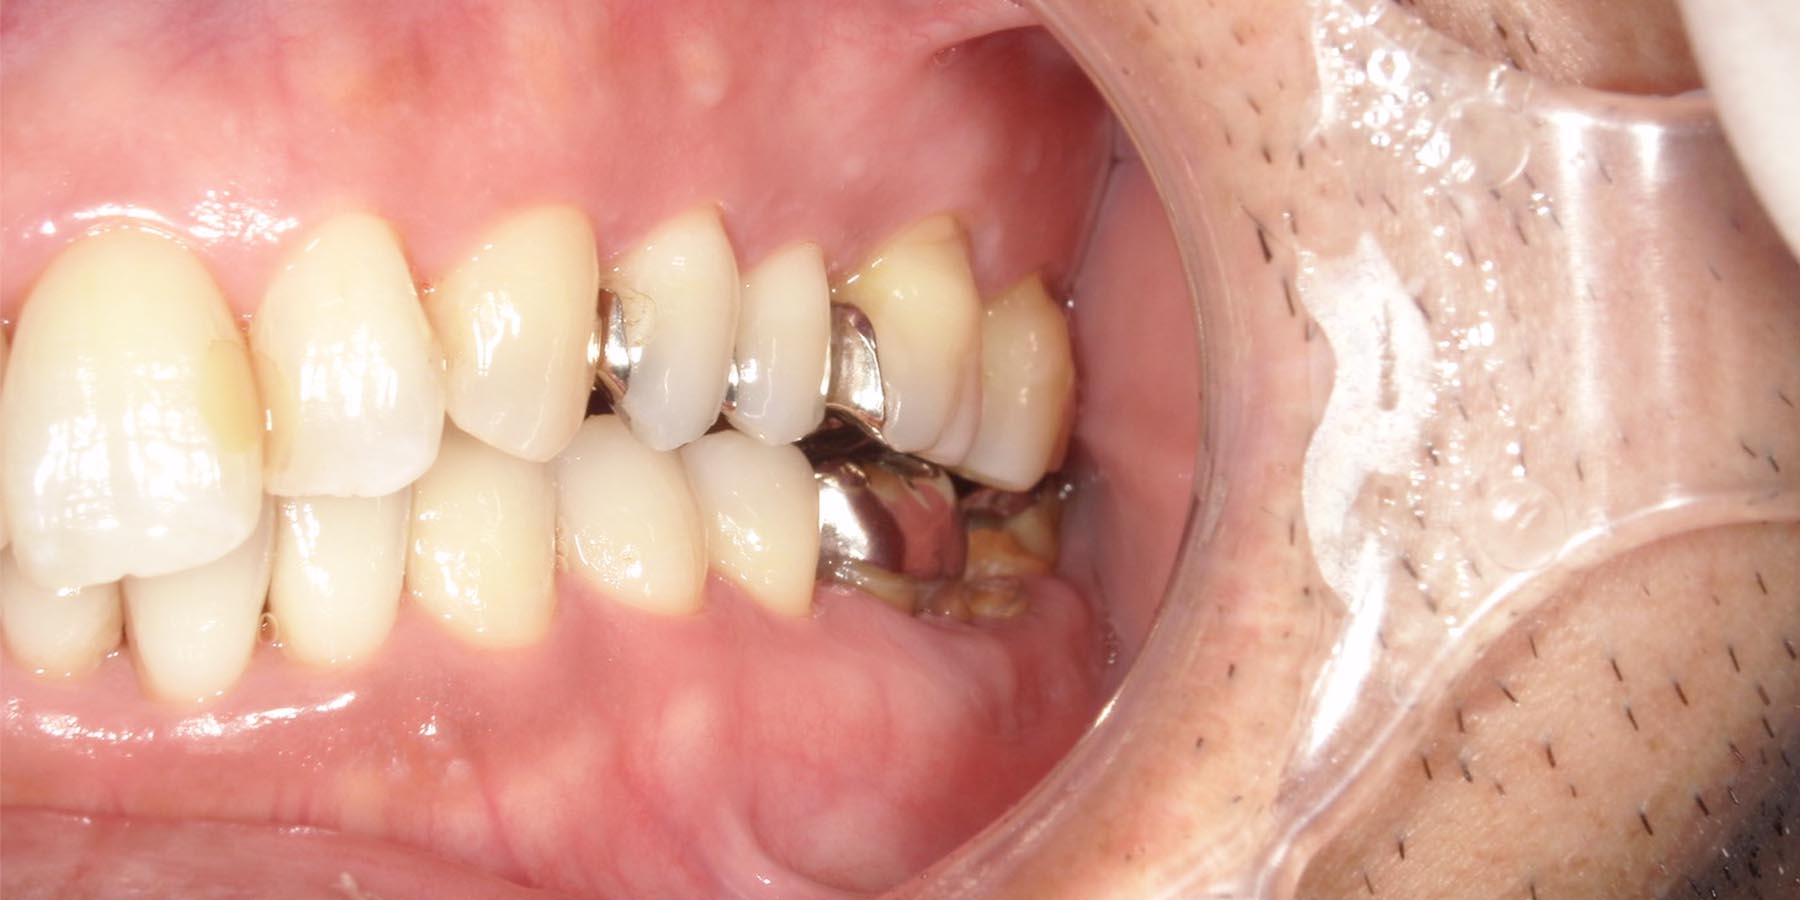

治療前